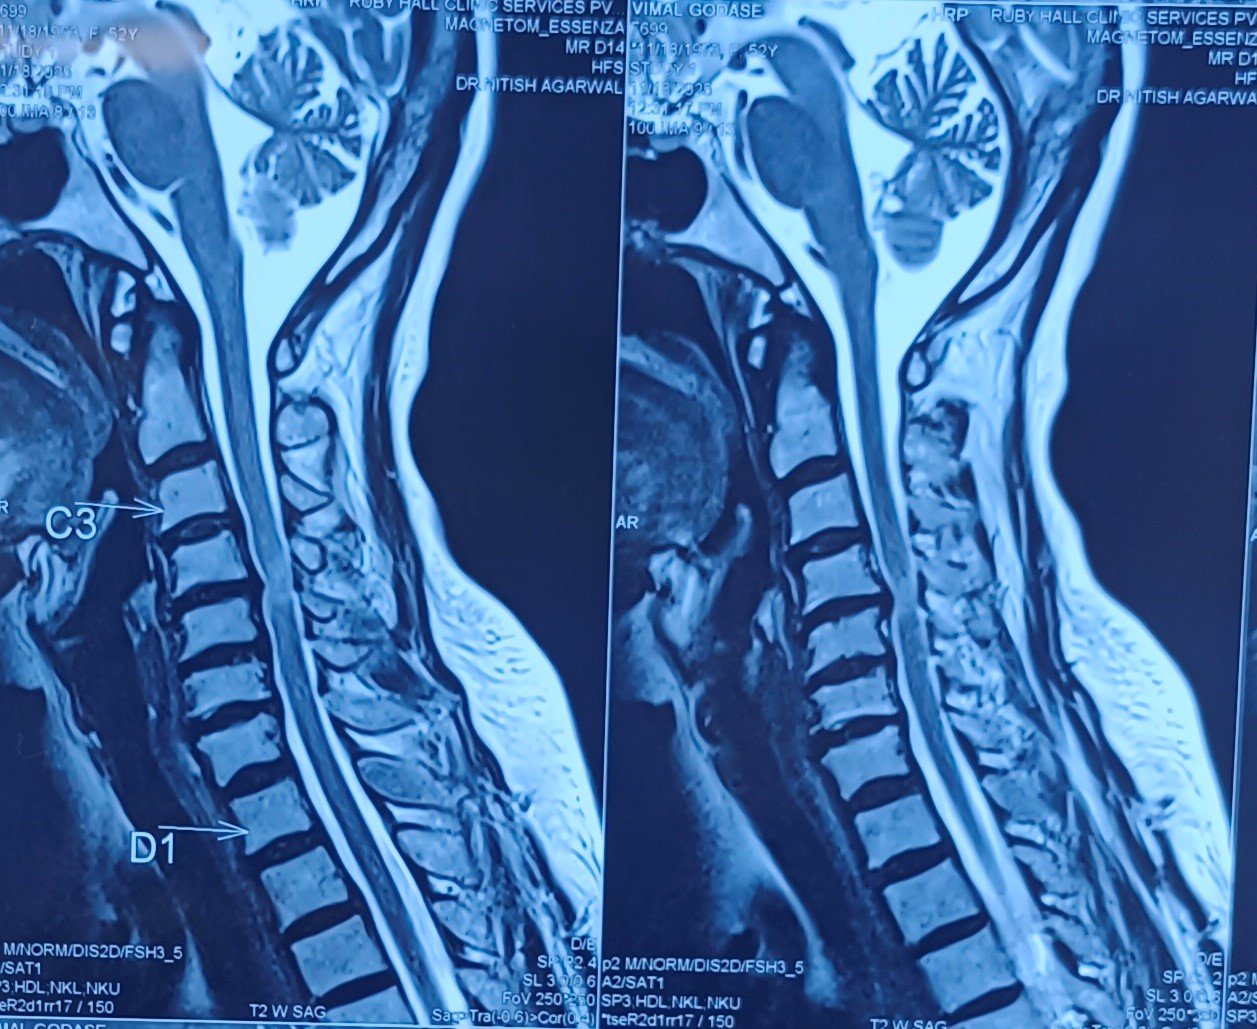

Cervical Disc Prolapse with Spinal Cord Compression

Special Cases Cervical Disc Prolapse with Spinal Cord Compression Condition:Cervical disc prolapse in which the herniated disc compresses the nerve roots and spinal cord, often associated with spinal cord edema. Symptoms:Neck pain, numbness in hands, weakness, difficulty in walking, and coordination problems. Treatment:Anterior Cervical Discectomy and Fusion (ACDF) – The…